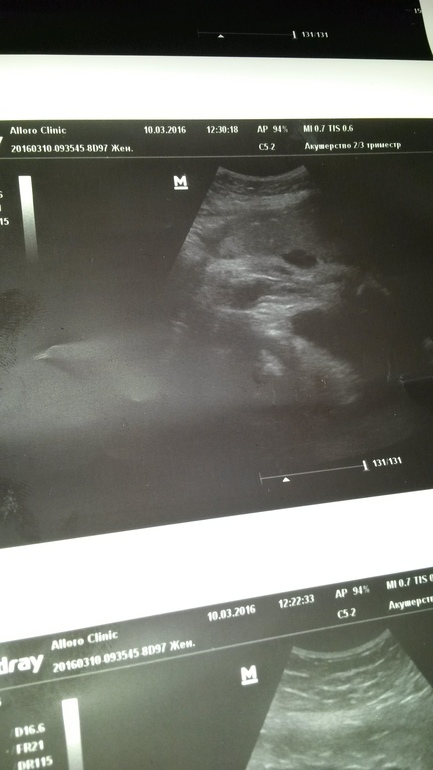

Узи 31 неделя.Как думаете кто же?)

Похоже на девочку.

девочка!

Я думаю девочка, однозначно!

Это девочка!! "Валик" сетно видно

У нас похожее фото в 20 недель, сказали что девочка))

Девочка. У моих трёх хозяйство было видно, не перепутаешь, а тут я не вижу)) точнее наоборот - девочку вижу))))